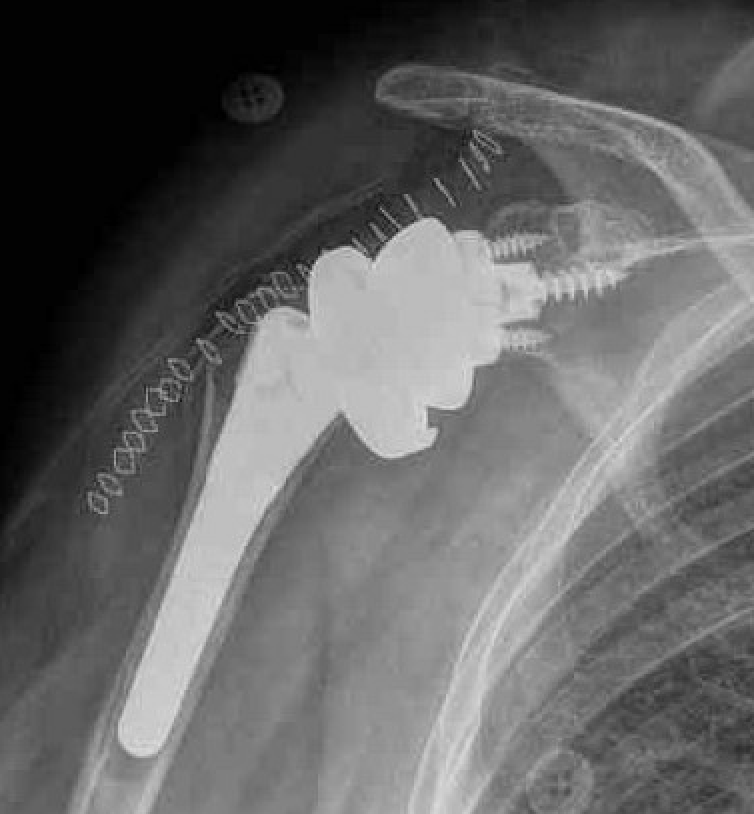

Reverse shoulder arthroplasty

Reverse

- socket in proximal humerus

- ball in glenoid

- center of rotation shifted medially and distally

- allows deltoid to apply compressive force and stabilize joint in absence of rotator cuff

Paul Grammont in 1985

- humeral component concave

- glenoid component / glenospere convex

- glenoid component uncemented with peripheral screws and central plug

- center of rotation shifted medially to glenosphere with humerus distal